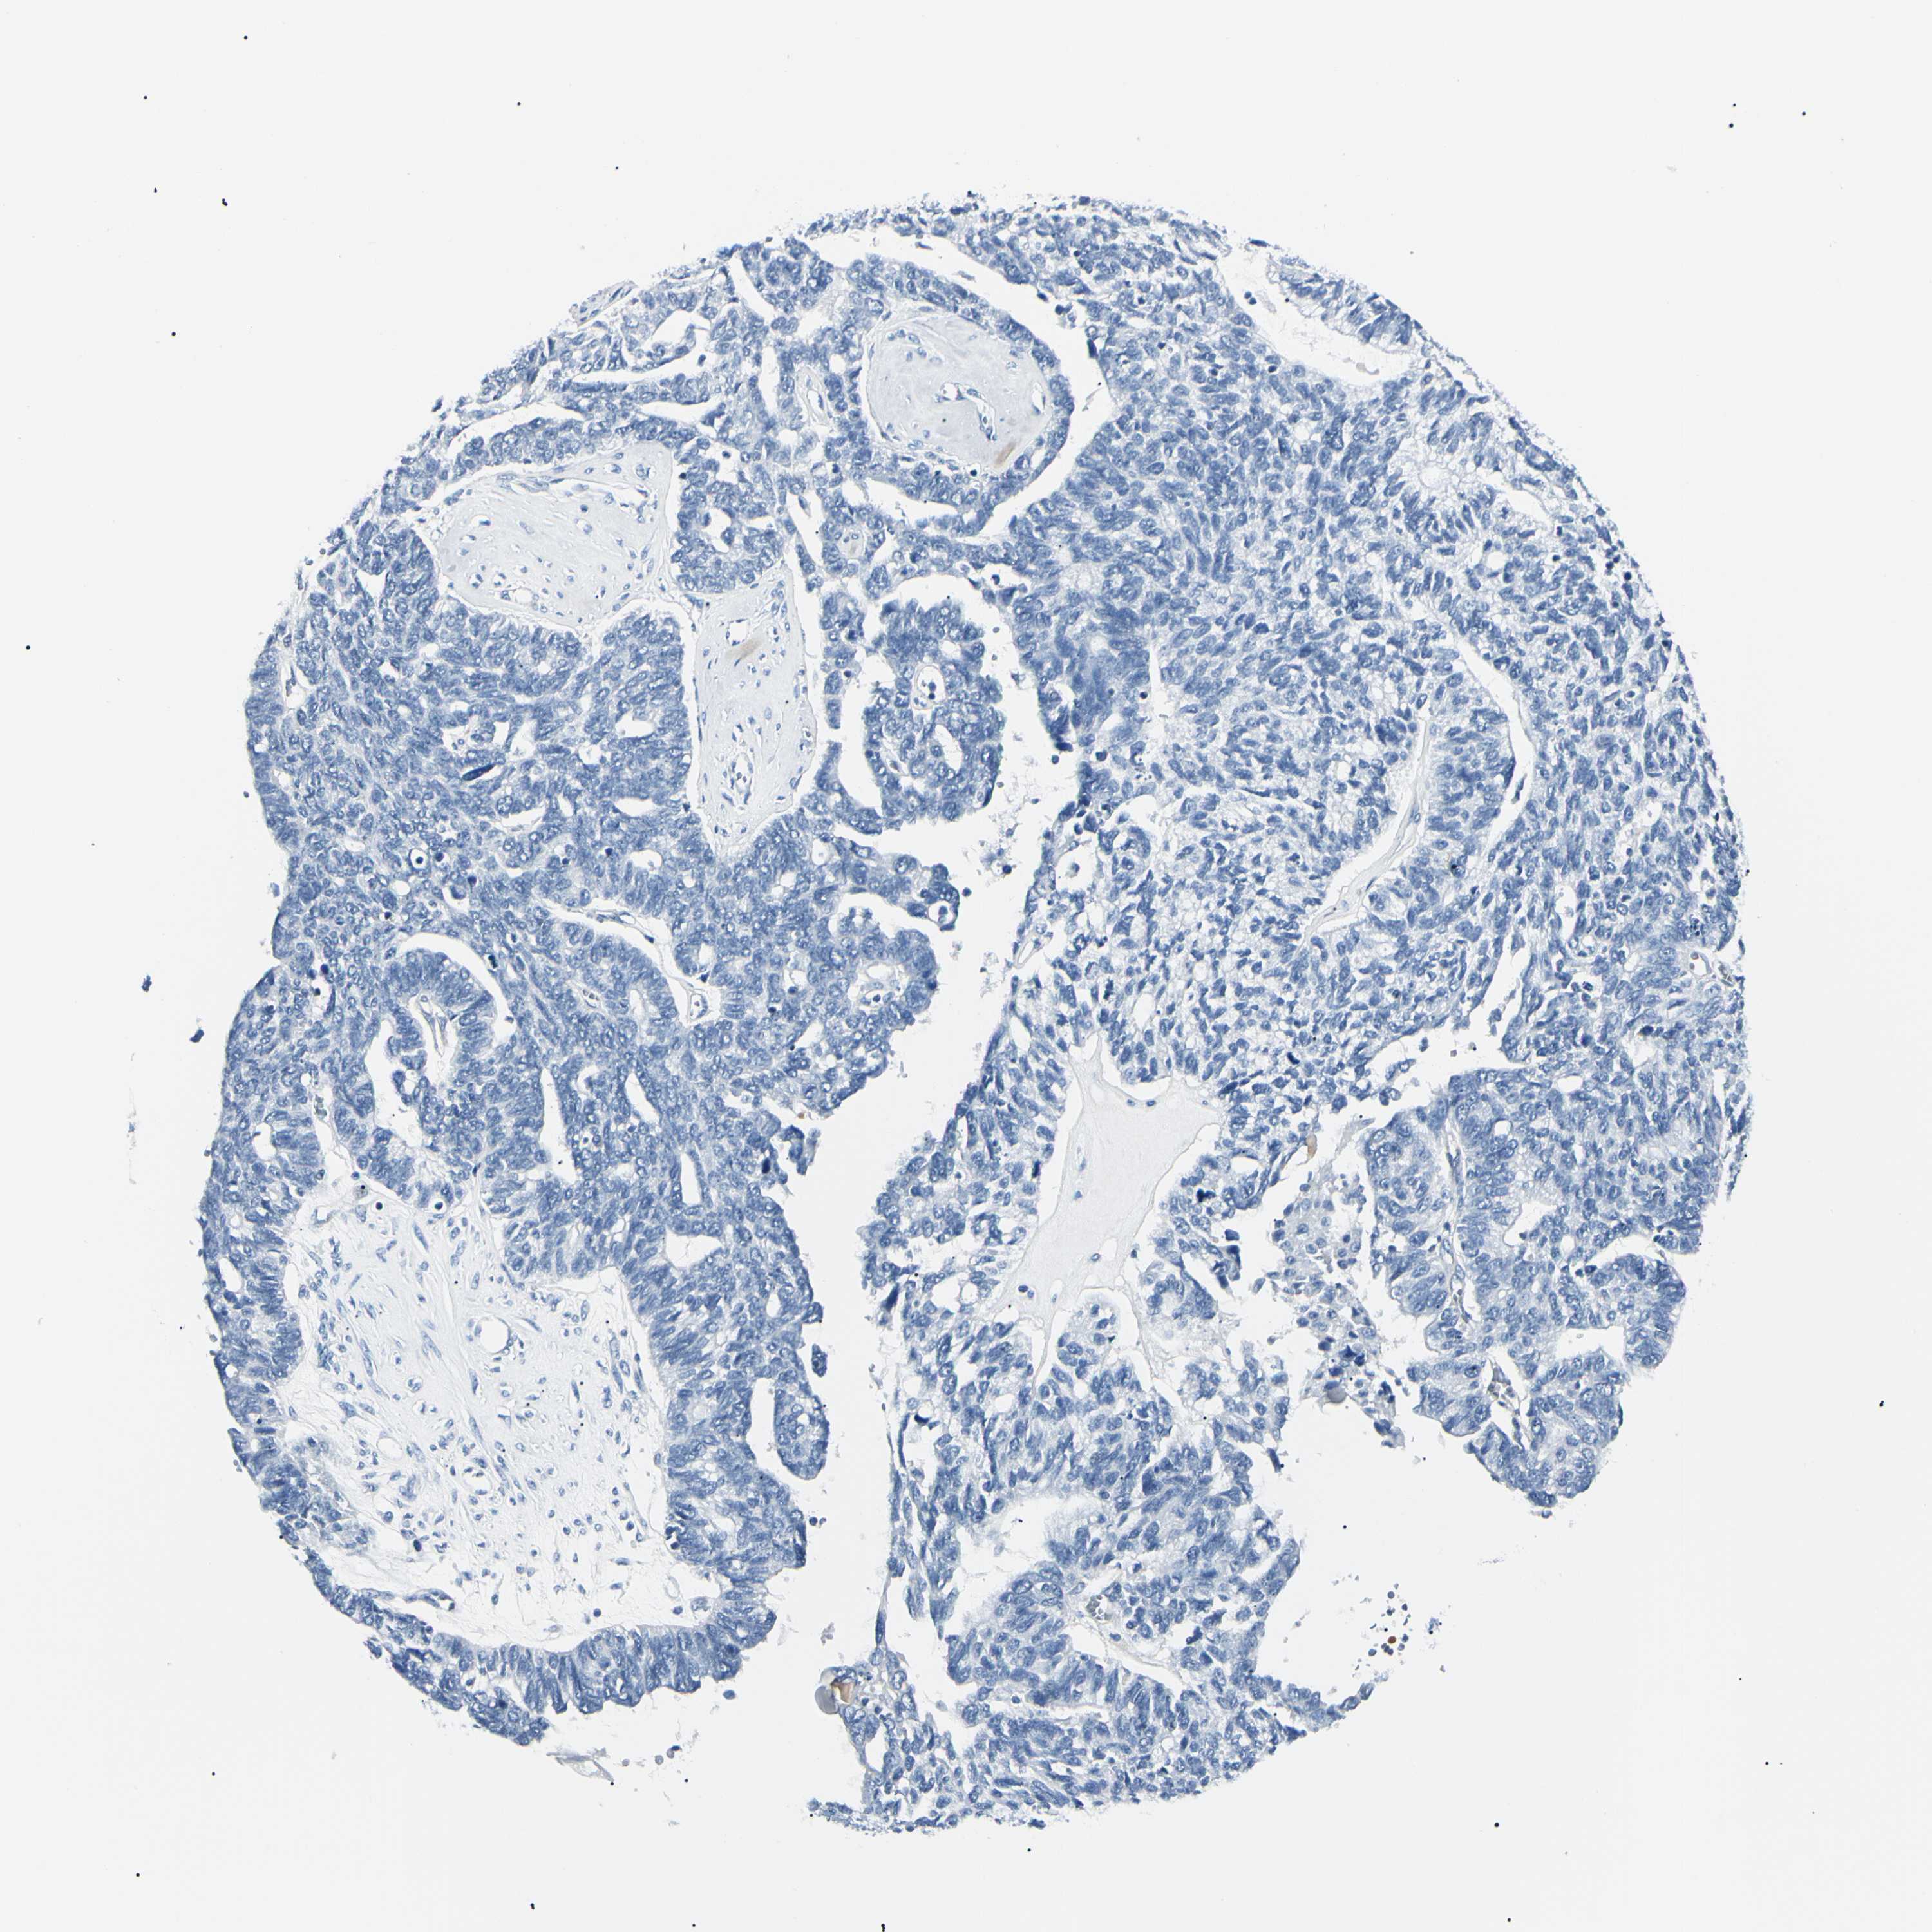

OVARIAN CANCER - Protein expressioni

A mouse-over function shows sample information and annotation data. Click on an image to view it in a full screen mode. Samples can be filtered based on level of antibody staining by selecting one or several of the following categories: high, medium, low and not detected. The assay and annotation is described here.

Note that samples used for immunohistochemistry by the Human Protein Atlas do not correspond to samples in the TCGA dataset.

Antibody stainingi

Antibody staining in the annotated cell types in the current human tissue is reported as not detected, low, medium, or high, based on conventional immunohistochemistry profiling in selected tissues. This score is based on the combination of the staining intensity and fraction of stained cells.

Each image is clickable and will lead to virtual microscopy that enables deeper exploration of all samples and also displays staining intensity scores, fraction scores and subcellular localization as well as patient and tissue information for each sample.

Antibody HPA001550

Antibody CAB010102

Carcinoma, endometroid

Cystadenocarcinoma, serous, NOS

Cystadenocarcinoma, mucinous, NOS

Carcinoma, NOS